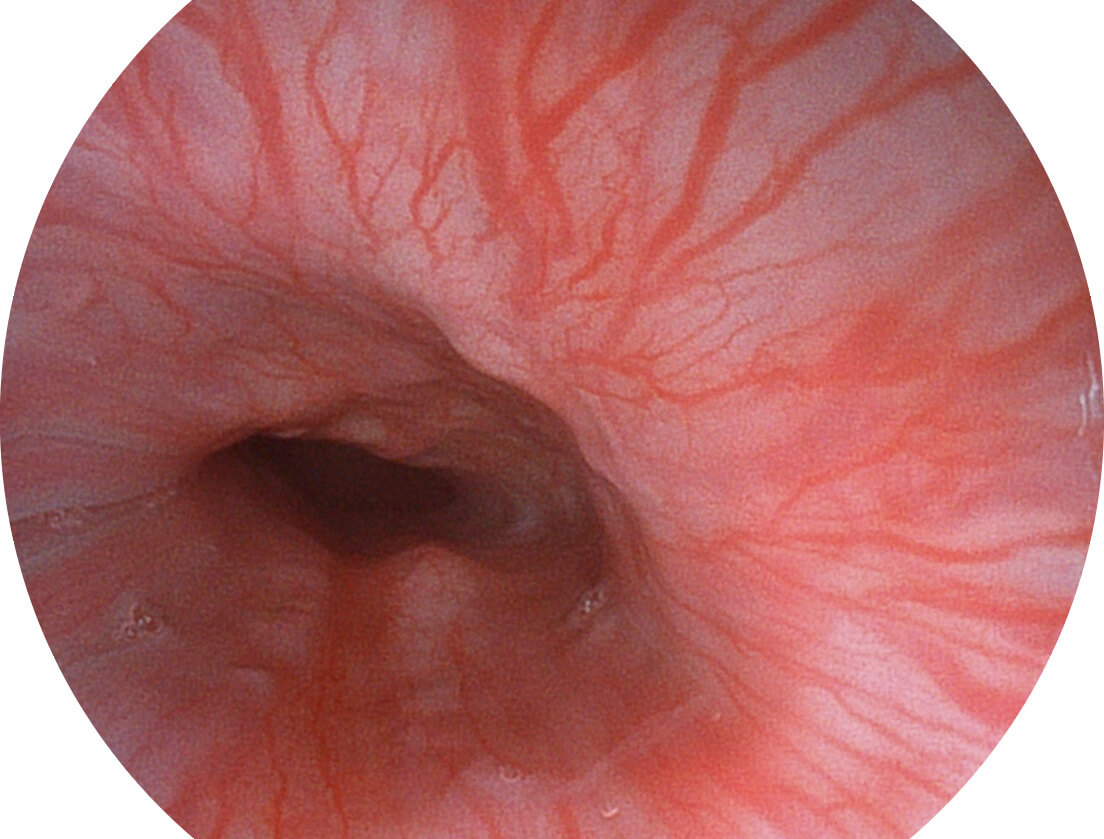

白光图像

白光图像

SFI图像

SFI图像

白光图像

白光图像

SFI图像

SFI图像

白光图像

白光图像

SFI图像

SFI图像